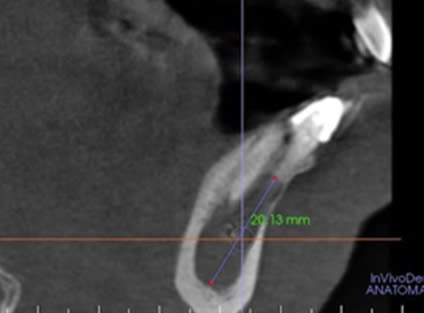

Hình 1. CBCT trước điều trị, bệnh nhân Đ.Q.Q